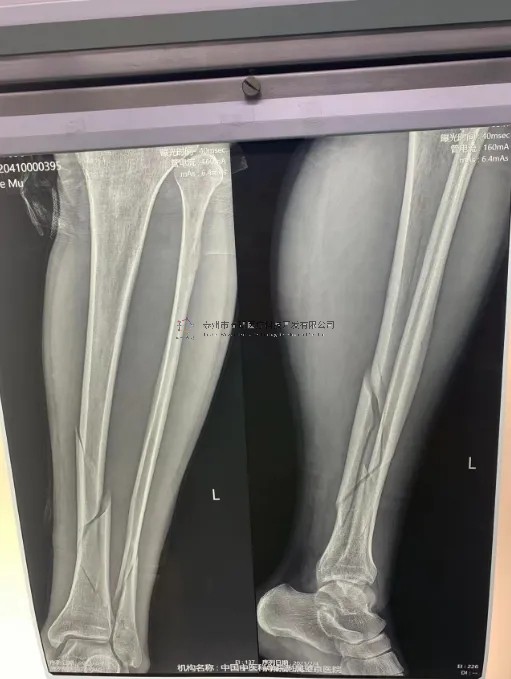

【患者情況】左脛腓骨近端骨折

【影像圖片】